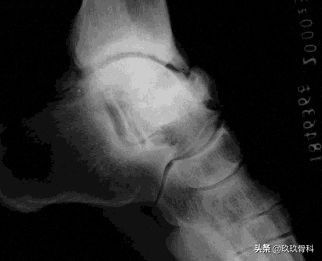

- X线 踝关节正侧位(必要时应加照踝穴位)

应力位片

诊断:体检—疼痛肿胀压痛的部位在踝的前上方;X线—踝内旋20°正位